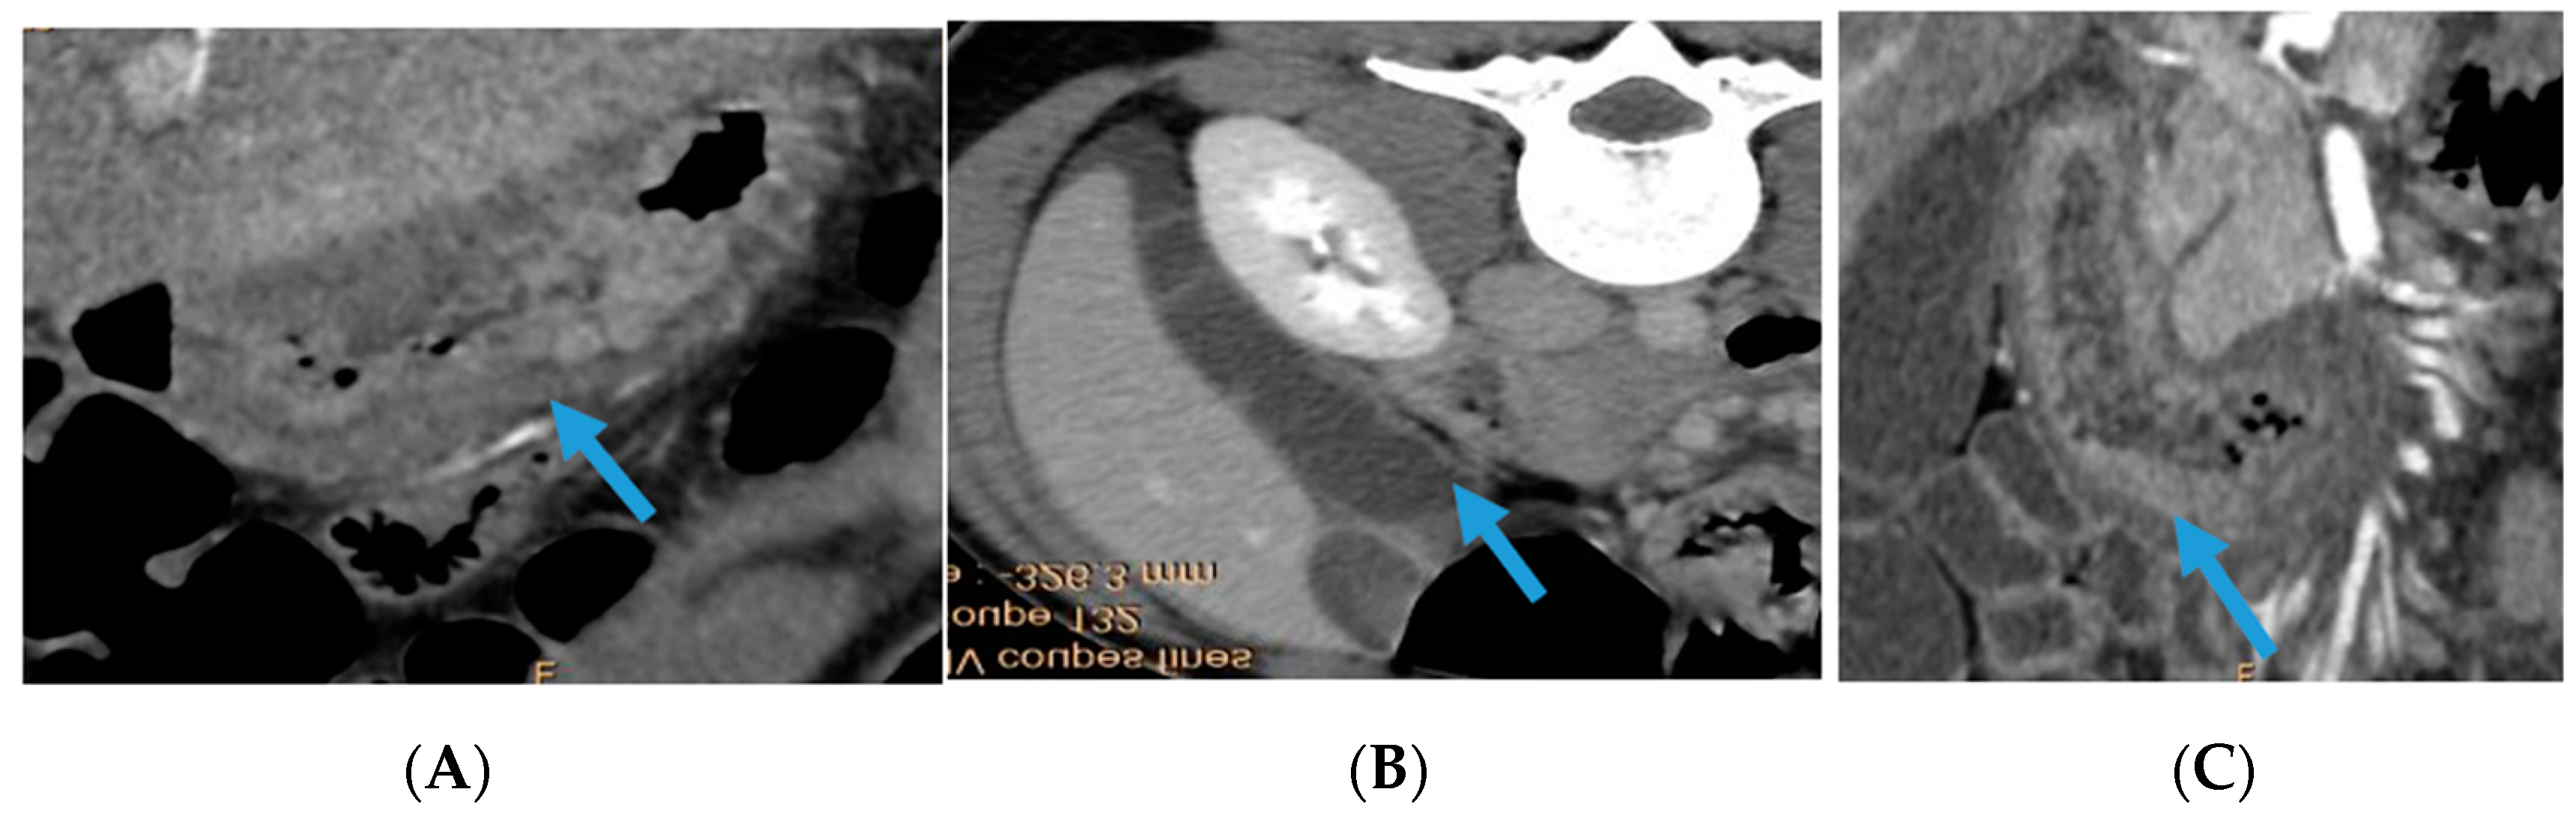

2. Case Report

| Intestinal wall thickening | + | - | + | + | + | + | + | + | + |